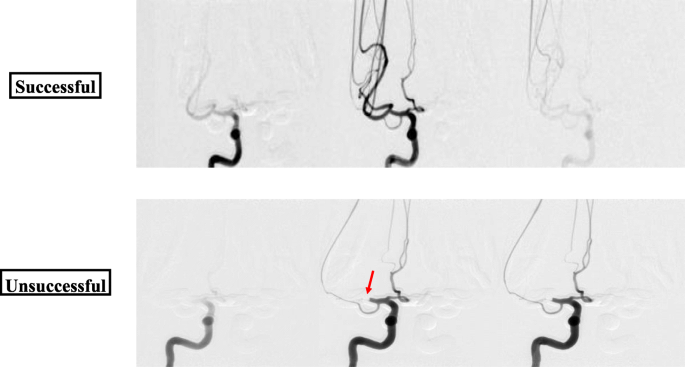

Using these phantoms, angiograms were captured before recanalization, showing the extent of the thrombus, and after the thrombectomy to determine the recanalization outcome. Figure 5 displays the change in blood flow before and after the stent retriever has been deployed. Figure 6 depicts a montage of the contrast flowing through a 3D printed model after both an unsuccessful and a successful mechanical thrombectomy simulated procedure.

Angiograms were taken post-stent retriever thrombectomy for each of the cases. A successful case and an unsuccessful case are displayed above. The successful case shows contrast flowing through the neurovascular phantom resulting in no occlusion. While the unsuccessful case shows the contrast flow being halted where the blood clot is still blocking the vessel resulting in full occlusion (red arrow)